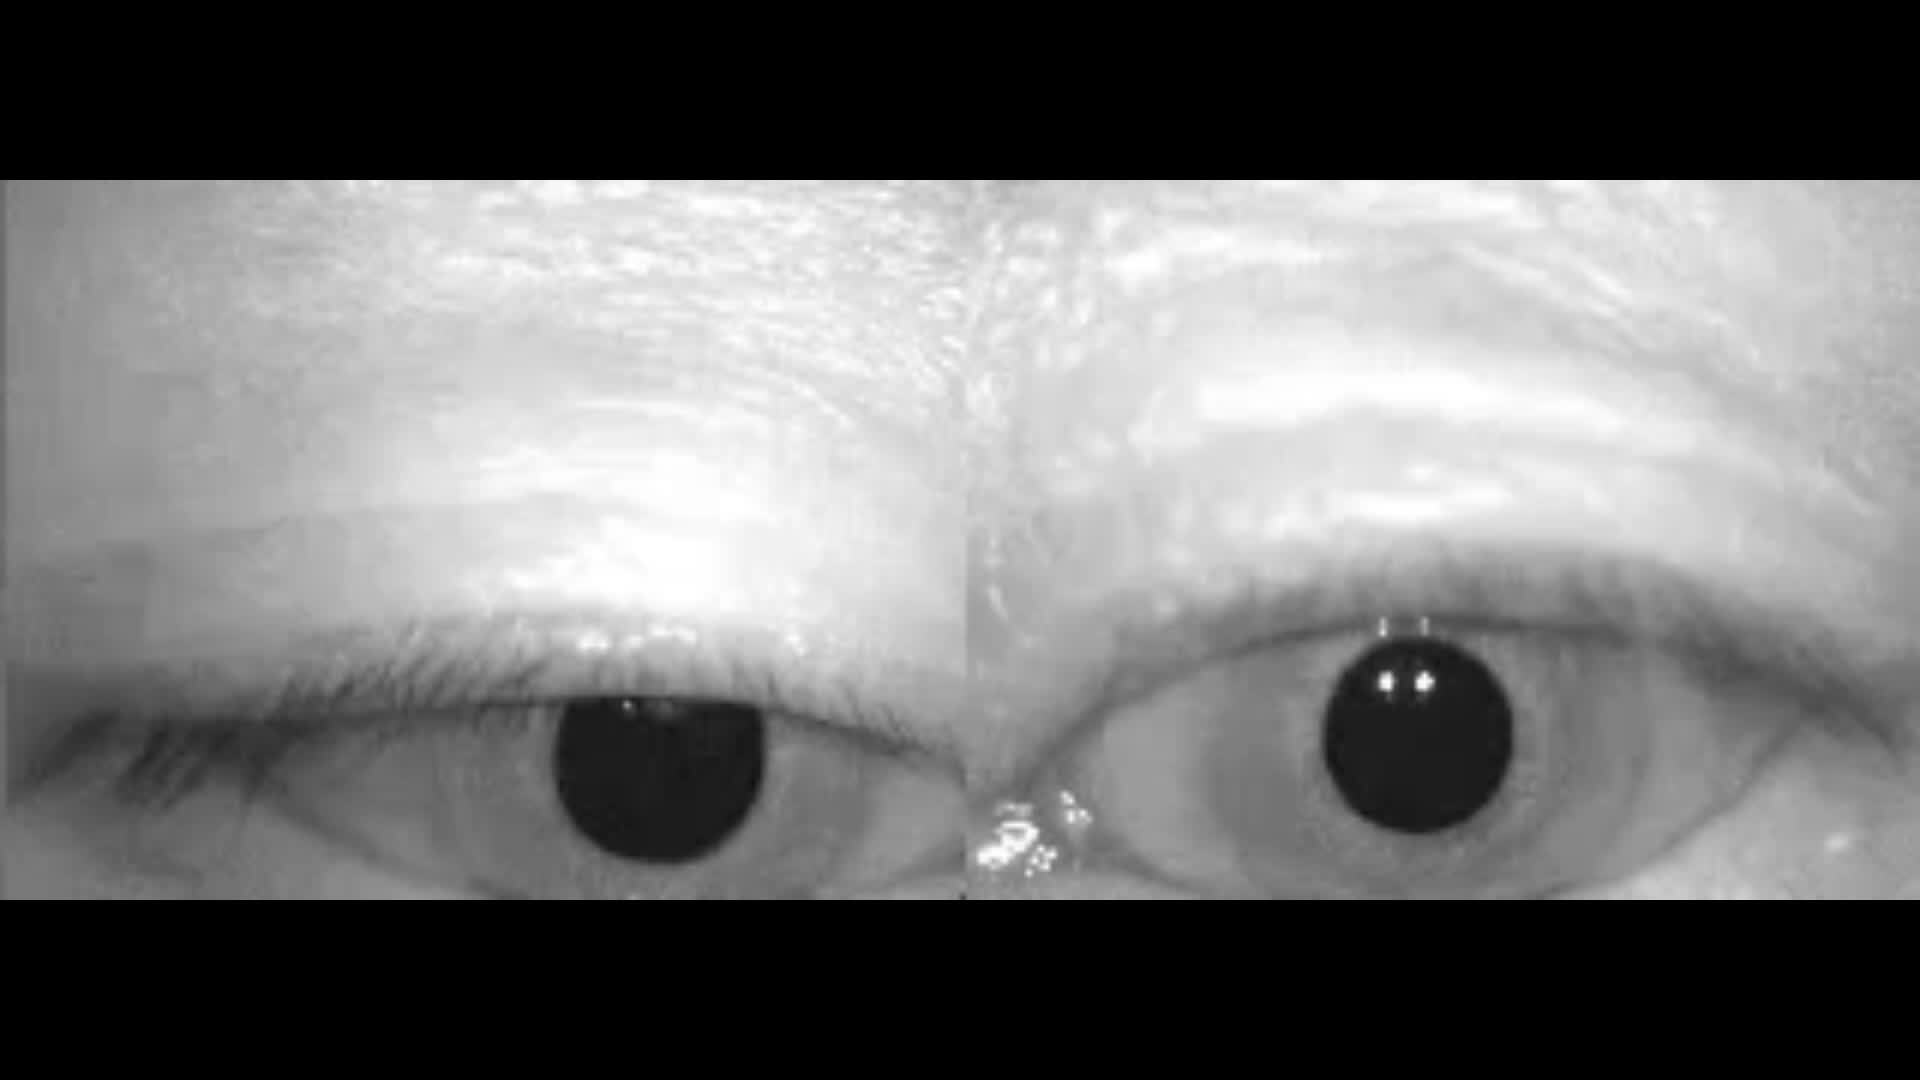

第二常见的耳石症是后半规管耳石症,患者表现为坐卧为改变时出现头晕眩晕,下面的视频是一例右后半规管耳石症患者迅速躺下时的眼震,眼睛上跳,右侧旋转。